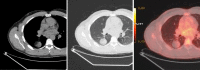

Current widespread use of cross-sectional imaging has led to exponential rise in detection of solitary pulmonary nodules (SPNs). Whilst large numbers of these are benign 'incidentalomas', lung cancers presenting as SPNs are often early disease, which have good prognosis. Therefore, there is rising demand and expectation for more accurate, non-invasive, diagnostic tests to characterize SPNs, aiming to avoid missed or delayed diagnosis of lung cancer. There are wide differential diagnoses of benign and malignant lesions that manifest as SPNs. On conventional imaging, the morphological features supporting benignity include stable small nodule size, smooth demarcated margins, and calcifications. Lack of significant contrast enhancement is also more suggestive of benign nodules. With improved understanding of tumor biology, for instance neo-vascularization and increased vascular permeability, imaging techniques such as dynamic contrast-enhanced computed tomography (CT) provide details on contrast uptake and wash-out kinetics, which is more closely reflecting the physiological and pathological phenomena. Positron emission tomography (PET) using 18fluorine-fluoro-deoxyglucose ((18)F-FDG) is a well-established functional imaging technique, for which one of the most common indications is differentiating between benign and malignant SPNs. Combined PET-CT integrates the anatomical, morphological and metabolic aspects in a single examination, improving overall diagnostic accuracy. Semi-quantitative analysis in FDG-PET imaging is based on measurement of maximum standardized uptake values (SUVmax). SUVmax analysis may become more useful as an assessment of tumor biology in future risk stratification models for cancers. Dual-time point FDG-PET imaging, dual-energy CT, perfusion CT, magnetic resonance (MR) imaging using dynamic contrast enhancement or diffusion-weighted imaging (DWI) techniques, are among the growing armamentarium for diagnostic imaging of SPNs. Provided there is no unacceptably high procedural or operative risk, tissue diagnosis by resection or percutaneous biopsy of SPN should be advocated in those patients identified as at moderate or high risk of malignancy, based on clinical stratification.